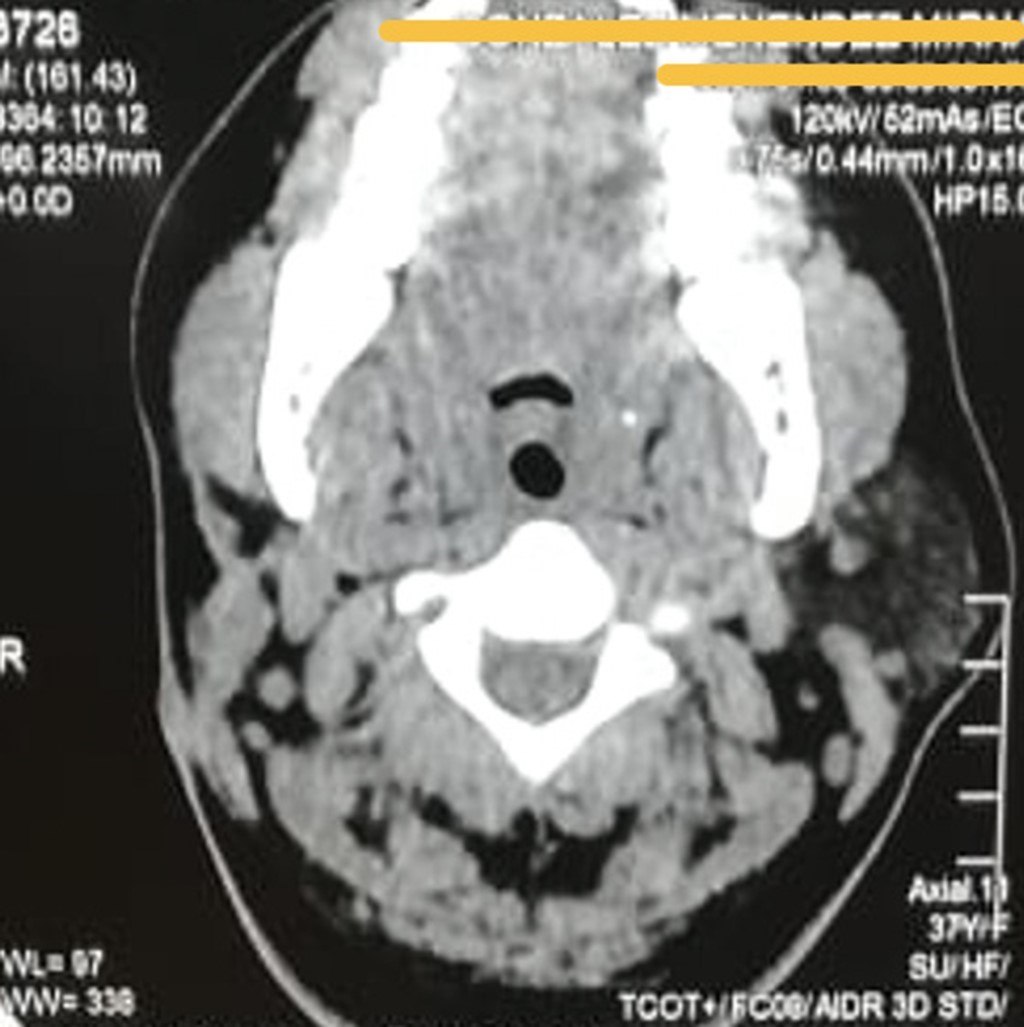

Figure 1

Figure 2

Figure 3

Figure 4

Figure 5

Figure 6

Figure 7

Figure 8

Figure 9

Figure 10

Figure 11

Figure 12